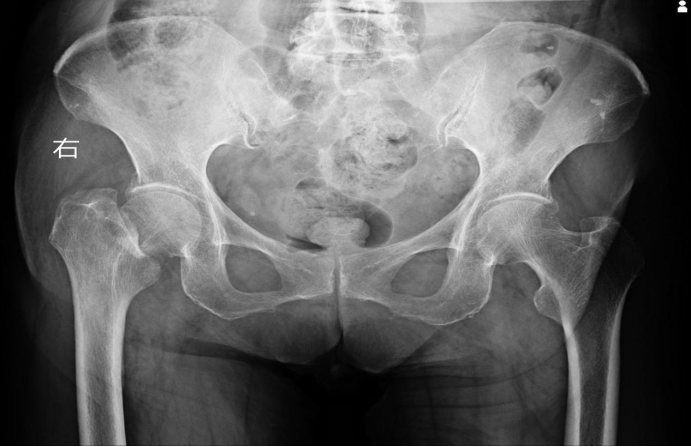

患者女性,96岁,因摔伤致右髋部疼痛畸形、无法行走,于9月2日入住重庆市九龙坡区中医院骨伤科一病区。经X线及CT检查,诊断为“右侧股骨颈骨折(头下型 Garden IV型)”,属于最严重的骨折类型。骨伤科一病区接诊团队迅速评估病情:若采取保守治疗,老人将面临长期卧床的困境,褥疮、肺炎、深静脉血栓等并发症随时可能危及生命。而手术则意味着要直面高龄患者心肺功能衰退、麻醉耐受性差、术后康复难度大等重重挑战。

(术前X片)